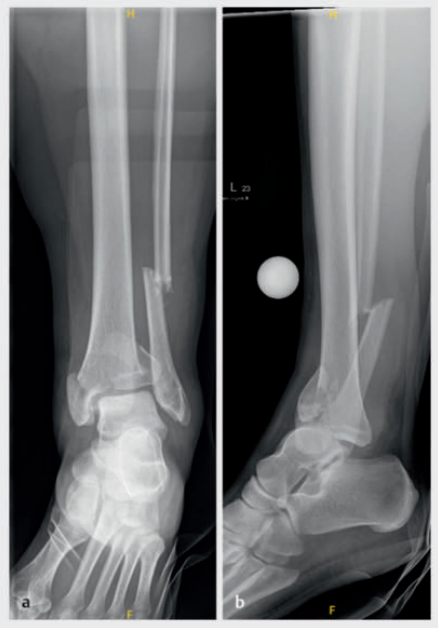

病例2受伤后入院首先植入跨踝关节外固定架,待软组织肿胀消退后,先对腓骨骨折进行微创固定,随后逐步完成复杂的胫骨Pilon骨折复位与固定。